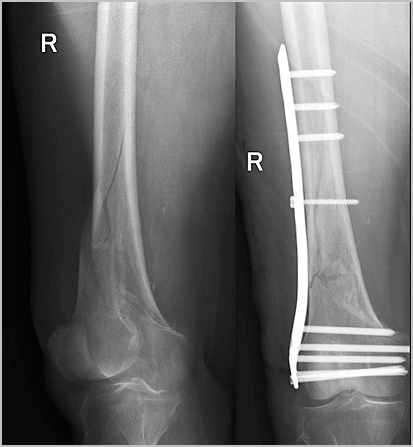

Фиксация отломков